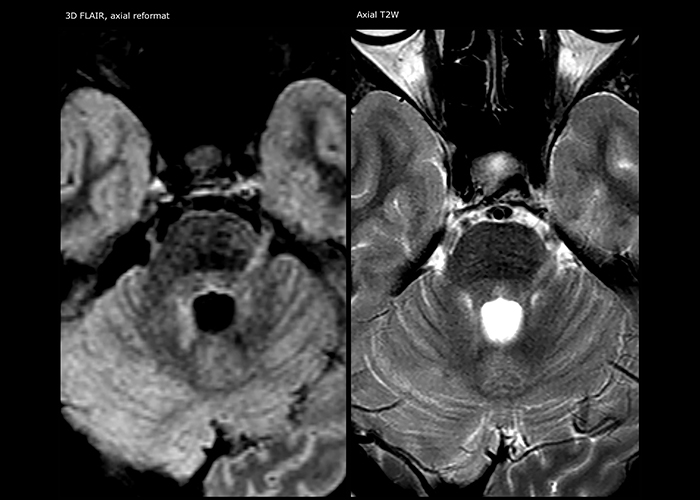

Every minute counts in stroke imaging

“In France, stroke is usually imaged with MRI, not CT, even for emergency treatment. This is because MRI helps us directly visualize ischemia in the acute phase, but can also help rule out differentials such as MS and hematoma. In addition, we can assess the intracranial and extracranial vessels during the same examination,” says Dr. Savatovsky.

The first challenge in MRI of stroke is speed. The patient typically arrives from an ambulance in the MRI preparation room and the installation is done on a separate dock outside the scanner room. “The venous access is placed during the neurological examination. If the delay from the first symptoms allows the patient to receive thrombolysis we do a very fast examination that typically lasts about 11 minutes including the pre-scans. In the case of transient ischemic stroke we usually add ASL perfusion because in some symptoms with negative diffusion, ASL sometimes indicates a vascular origin.”

“Ingenia provides great flexibility in the parameters setting. We can tune a sequence the way we want,” says Dr. Savatovsky. “For example, in a stroke exam we use a FLAIR sequence of about two minutes instead of the four-minute FLAIR we use for MS. The diffusion is 30 seconds, the T2*-weighted scan is 30 seconds, the angiography scan time is less than one minute. Ingenia is a great scanner in that situation; even with these fast sequences we can achieve good images with good SNR. When the first sequence tells us that it’s not an ischemic stroke but a hemorrhagic stroke, we may switch to a time-resolved angiography to look for vascular malformations and venous thrombosis.

The ideal stroke protocol?

“Every center is different, but for me the ideal protocol for stroke includes diffusion weighted imaging, FLAIR, and fast susceptibility imaging,” says Dr. Savatovsky. “Our fast susceptibility weighted imaging takes 50 seconds, so it’s as fast as T2*-weighted imaging. It visualizes hemorrhage but also the clots. We also do 3D MR angiography that provides information on cervical and brain vessels. If the patient does not need immediate treatment, or if additional information is needed to decide on treatment, we might also add perfusion imaging and post-contrast T1-weighted imaging.”